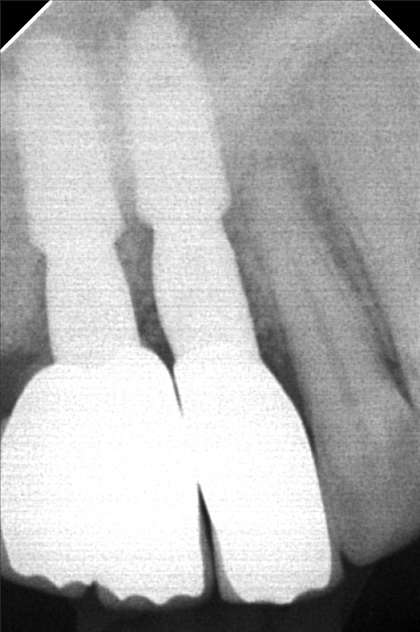

Edit Record Check our patient data records. Add patient information Patient Info Profile picture Last Name First Name Middle Name Birthdate Age Street Barangay City Country Zip Code Contact number Email Procedure 01/30/21 ICF - check up Feb 8,2021 - Implant 11/03/22- OP/OZONE/PAD feb,20,2021- removal of suture march 31,2021- LC 11 & 21 07/31/21 repair 41 zirconia resto 36CAOH/46 CAOH/43/34 OP June 4,2022 - OP / Xray 05/13/23- OP(Moderate); xray; ozone Oct 1 2023 op with air polisher noticed gum recession Removal of fiber splint on 42/43 05/07/24 Air polisher Xray OP 06/15/24 connective tissue graft harvested side: upper right quadrant w/ suture- monofilament absorbable 4/0 donor site: implant #41/32 buccal and lingual combination of monofilament absorbable 4/0 and nylon 6/0 non absorbable 06/22/24 check up 06/29/24 suture removal File raposa_donna_kelly_3.jpg File 2 raposa_donna_kelly_2.jpg File 3 raposa_donna_kelly_1.jpg File 4 donna_kelly.jpg File 5 june_42022.jpg File 6 raposa_donna.jpg File 7 raposa_donna_02.jpg File 8 img_2831.jpg File 9 File 10 File 11 File 12 File 13 File 14 File 15 File 16 File 17 File 18 File 19 File 20 Retain Record Retain Record Yes No Save Your Changes